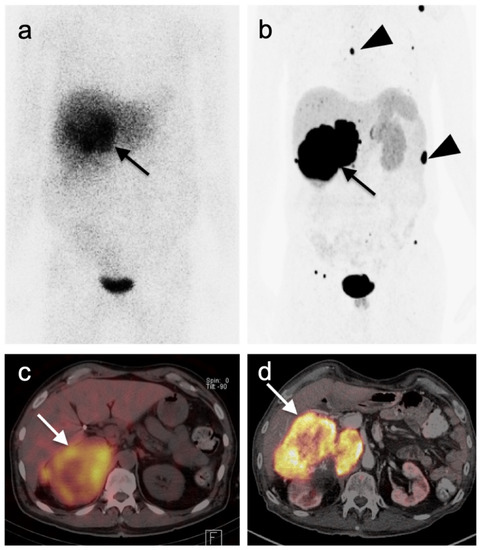

- Gao, Y.-J.; Yang, Z.; Yu, J.-Y.; Li, N.; Wang, X.-J.; Zhou, N.-N. Potential application value of PET/computed tomography in retroperitoneal leiomyosarcoma and a literature review. Nucl. Med. Commun. 2021, 42, 800–810. [Google Scholar] [CrossRef]

- Subramaniam, S.; Callahan, J.; Bressel, M.; Hofman, M.S.; Mitchell, C.; Hendry, S.; Vissers, F.L.; Van der Hiel, B.; Patel, D.; Van Houdt, W.J.; et al. The role of 18 F-FDG PET/CT in retroperitoneal sarcomas—A multicenter retrospective study. J. Surg. Oncol. 2021, 123, 1081–1087. [Google Scholar] [CrossRef]